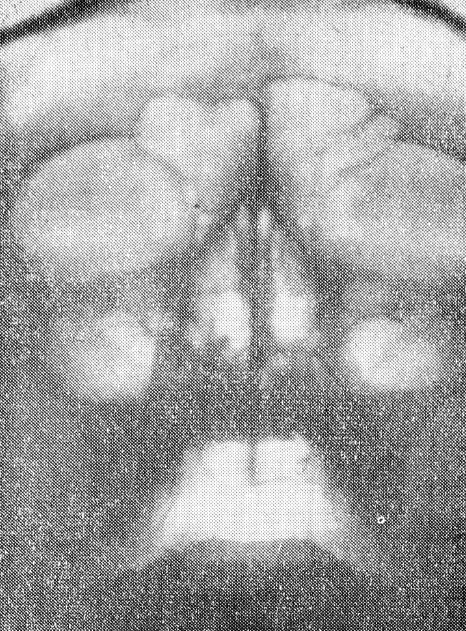

При помощи данного приспособления можно производить снимки придаточных пазух в вертикальном положении больного на аппаратах всех систем, внося при необходимости несущественные изменения. Мы производили снимки на аппарате УРДд-110-К4 при режиме: большой фокус, 67 кв, 50 МА, экспозиция 2,5 сек, фокусное расстояние 67 см (рис. 3, 4).

Рис. 3. Снимок при горизонтальном положении больного. Жидкость в пазухах не определяется.